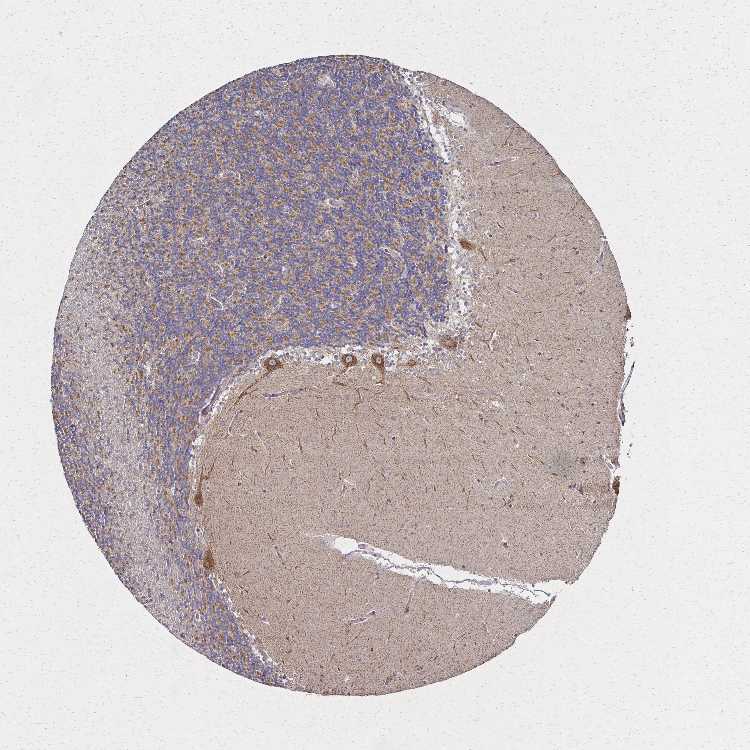

CEREBELLUM - Antibody stainingi

Antibody staining in the annotated cell types in the current human tissue is reported as not detected, low, medium, or high, based on conventional immunohistochemistry profiling in selected tissues. This score is based on the combination of the staining intensity and fraction of stained cells.

Each image is clickable and will lead to virtual microscopy that enables deeper exploration of all samples and also displays staining intensity scores, fraction scores and subcellular localization as well as patient and tissue information for each sample.

Antibody HPA051801Antibody HPA054755Antibody CAB034314

Bergmann glia - cytoplasm/membrane Not detected--

Bergmann glia - nucleus Not detected--

GLUC cells - cytoplasm/membrane High--

GLUC cells - nucleus Not detected--

Purkinje cells -HighMedium

Purkinje cells - cytoplasm/membrane High--

Purkinje cells - dendrites High--

Purkinje cells - nucleus Not detected--

Cells in granular layer -HighMedium

Cells in molecular layer -LowMedium

Granular cells - cytoplasm/membrane Low--

Granular cells - nucleus Not detected--

Molecular layer - neuropil Not detected--

Molecular layer cells - cytoplasm/membrane High--

Molecular layer cells - nucleus Not detected--

Processes in granular layer Not detected--

Processes in molecular layer Not detected--

Processes in white matter Not detected--

Synaptic glomeruli - capsule Not detected--

Synaptic glomeruli - core High--

White matter cells - cytoplasm/membrane Medium--

White matter cells - nucleus Not detected--